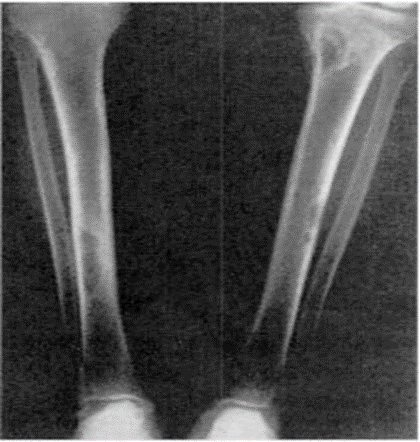

Xəstəliyin sümük forması 1891-ci ildə Recklinghausen tərəfindən verilmişdir. Bu sümüklərdə xüsusilə də onurğa və ətraf oynaqlarında ağrıların olması ilə xarakterizə olunur. Əvvəlcə ağrı ancaq hərəkət zamanı, sonra isə daimi olur və xəstədə "ördək" yerişi başlayır. Gec mərhələdə borulu sümüklərin qalınlaşması və əyilməsi, skeletin deformasiyası, patoloji sınıqların əmələ gəlməsi, dişlərin laxlaması və düşməsi baş verir.

Sümükdə baş verən osteodistrofiyanın mənşəyinin paratiroid olduğunu aydınlaşdırmaq üçün rentgenoqrafiya əsas metodlardan biridir (Şəkil 4).

Sümükdə baş verən dəyişikliyi şərti olaraq 3 qrupa bölmək olar:

- I tip klassik forma. Osteoporoz fonunda barmaq falanqalarında sümüküstlüyünün altında, sümüyün qabıq qatının parçalanması görünür. Bəzən seçici olaraq ikinci, üçüncü falanqa və bəzən də üçüncü falanqanın distal hissəsi parçalanmaya məruz qalır. Xarakterik əlamətlərdən biri rentgenoloji müayinədə barmaq falanqalarında “sümük şişlərinin” görünməsidir. Bunlar adətən çoxsaylı olur və skeletin müxtəlif nahiyələrində, ən çox da ətrafların borulu sümüklərində epifiz və metafiz sərhədlərində müşahidə olunur. Aşağı döş və bel fəqərələrinin osteoporotik zədələnməsi onların yastılaşması və onurğanın deformasiyasına səbəb olur (kifoz, skalioz).

- II tip osteoporotik forma. Bu generalizə olunmuş osteoporoz şəklində meydana çıxır.

- III tip Paget forma. Bu zaman kəllə sümüklərinin kompakt qatı qeyri-bərabər qalınlaşır. Kraniumda subperiostal rezorbsiya və sklerozun nəticəsi olaraq “duz-bibər” mənzərəsi əmələ gəlir. Bu zaman borulu sümüklərin kompakt maddəsi nazikləşir, falanqalar qəhvəyi şiş adlandırılan bir forma alır. Sümük toxuması fibroz toxuma ilə əvəz olunduqca oraya qansızma ilə bərabər hemosiderin də toplanır. Xəstələrin 30%-də osteopeniya əmələ gəlir.